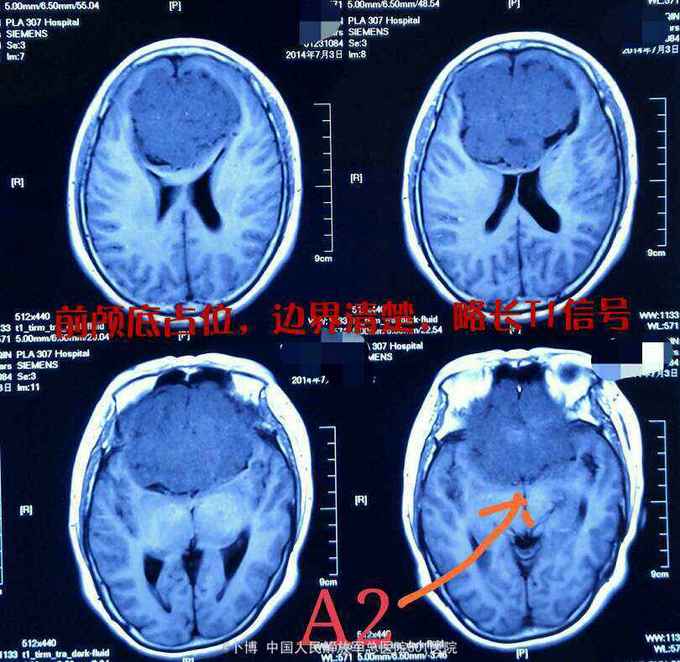

前颅窝底占位:脑膜瘤

脑膜瘤

前颅窝底占位:脑膜瘤。 手术入路:冠状切口,双侧额下入路肿瘤切除。

术后一年。复查MR示肿瘤全切。